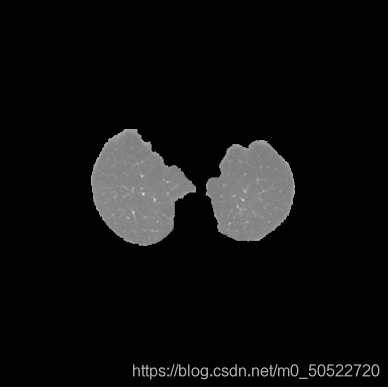

(6)消除气管

由上图可看出,虽然步骤5已经将肺质提取出来了,但是由于肺部中存在气管,所以在二值化以后会看到气管依然存在在二值图中,此时如果我们想得到没有气管的单独肺质时就需要对上图进行区域消除处理,定义一个适中的面积值,计算各连通区域的面积,由于肺质的连通面积较大,此时就使用定义的面积阈值,将小于此面积阈值的部分消除。即可得到单独的肺质如下图所示。